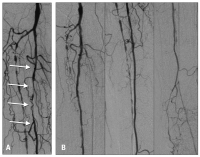

Ischämie

Abbildung 2a-b: A. Kritische Ischämie bei Verschluß der A. tibialis anterior und posterior sowie hochgradiger Stenosierung der A. fibularis (Pfeile). B. Ergebnis nach Laserrekanalisation der A. fibularis (1,7 mm Excimer-Laser) ohne Nachdilatation.